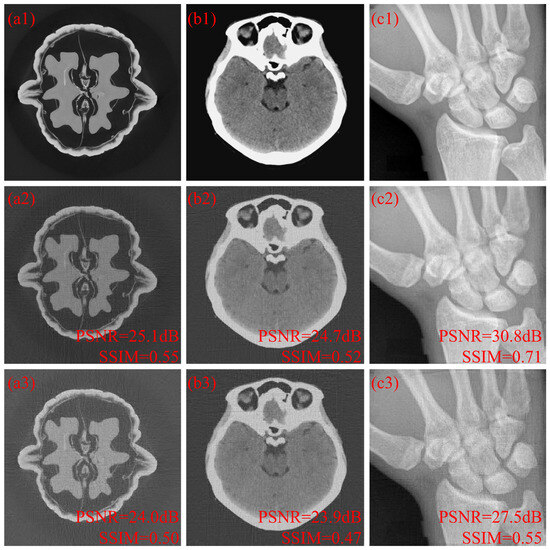

Coded Aperture Optimization in X-Ray Computed Tomography via Sparse Covariance Matrix Estimation

by Yuqi Jiang, Tianyi Mao, Jianyong Zhou, Qile Zhao, Jun Yin, Xuedong Yi and Haiyou Wu

Coded aperture X-ray computed tomography (CAXCT) measures coded X-ray projections to reconstruct the inner structure of an object. Coded apertures, which determine the point spread function, can be designed to improve the reconstruction quality, but most approaches are computationally expensive, leading to very [...] Read more.

Coded aperture X-ray computed tomography (CAXCT) measures coded X-ray projections to reconstruct the inner structure of an object. Coded apertures, which determine the point spread function, can be designed to improve the reconstruction quality, but most approaches are computationally expensive, leading to very small images. In this paper, a sparse covariance matrix estimation approach is introduced to minimize the information loss sensed by projections corresponding to large tomographic images. The covariance matrix representing the map of the overlapping information of the projections is obtained by using block matrix multiplication and sparse estimation. A heuristic variant algorithm with a noise factor is presented to search the combinations of D projections leading to maximum non-overlapping information acquisition, where D is the number of unblocking elements on the coded apertures. Numerical experiments with simulated datasets show that the optimization performance of the proposed method is comparable to that of state-of-the-art methods with small images. Further, for the analyzed cases, coded aperture optimization was performed with 512 × 512 images by analyzing coefficients smaller than 0.02% in the covariance matrix. Full article